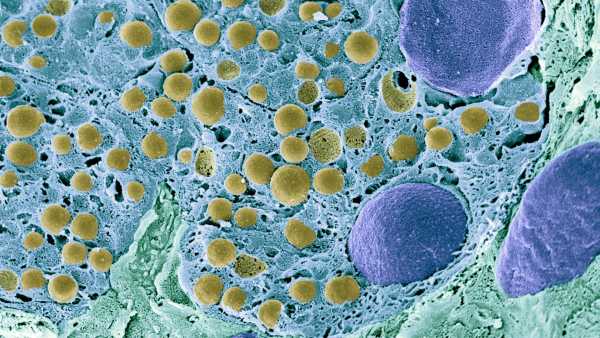

Старіючі клітини іноді називають «зомбі-клітинами», бо вони, своєрідно, нежить. Клітини перестають ділитися через стрес або пошкодження, але залишаються в організмі та спричиняють проблеми в контексті старіння. (Зображення: OsakaWayne Studios via Getty Images)